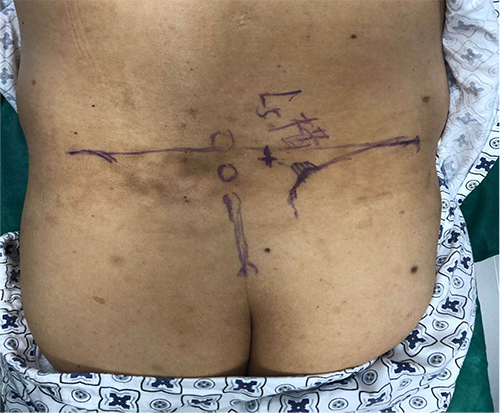

宋文阁教授为张大爷做了右侧L5横突和髂腰韧带处消炎镇痛液和臭氧注射,并在此处进行了小针刀松解。治疗刚结束,张大爷就感到疼痛得到了极大的缓解,翻身和起坐也不会再诱发腰疼。在后续巩固治疗后,张大爷带着满意的笑容出院了。